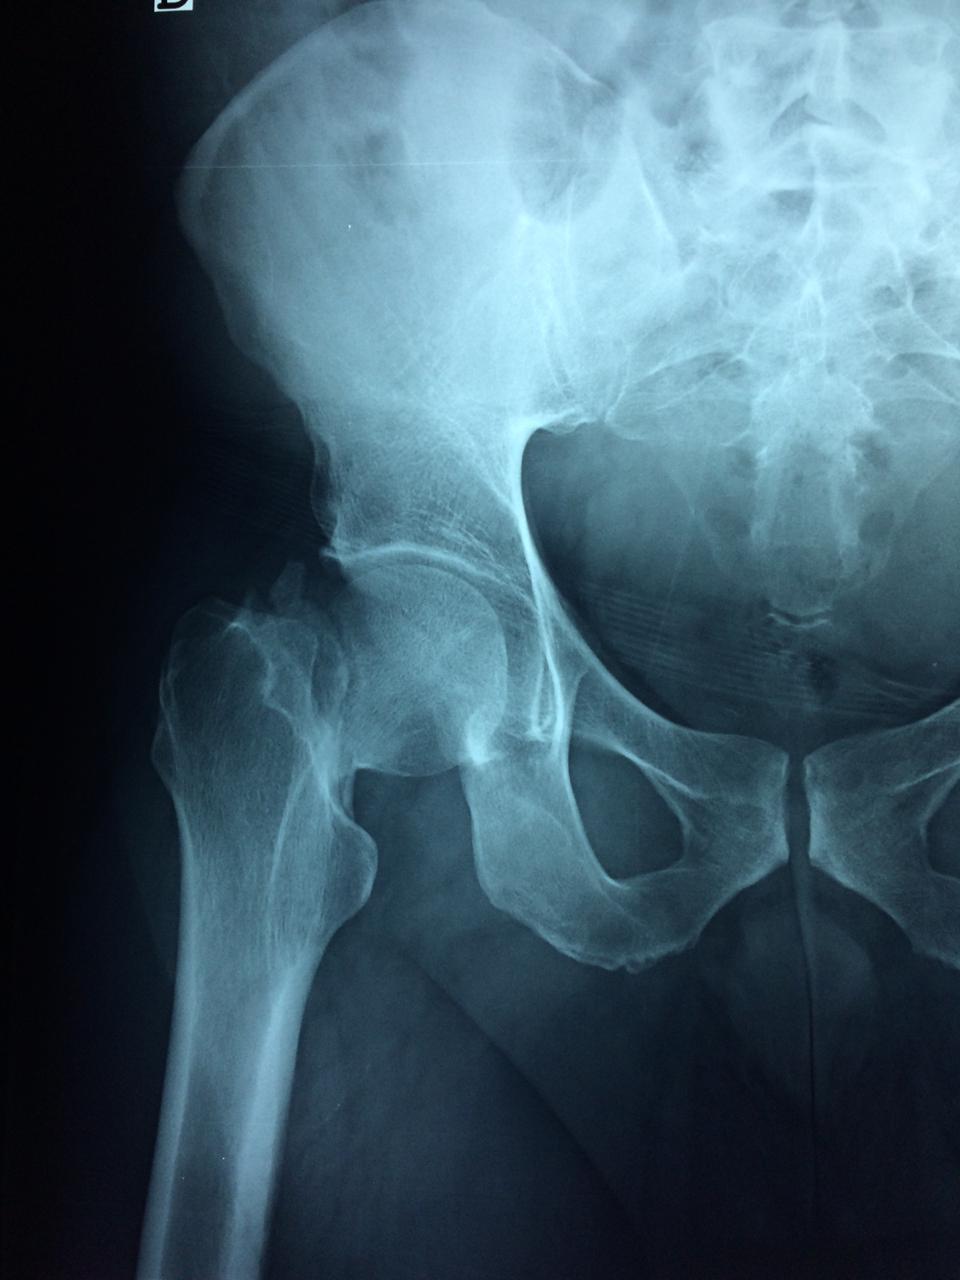

Fémur - Cadera

La cirugía de fractura de cadera se realiza para reparar una ruptura en la parte superior del hueso del muslo. Este hueso se denomina fémur.

Es parte de la articulación coxofemoral. Si una fractura de cadera no recibe tratamiento, es posible que deba permanecer en una silla o en la cama.